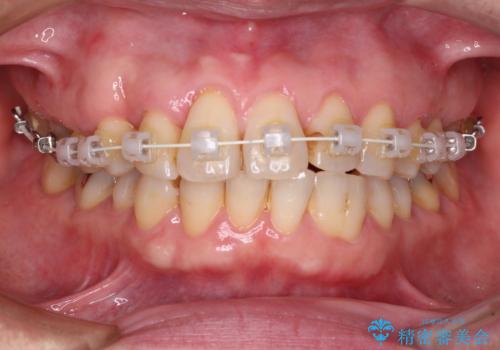

- 矯正装置

- 審美装置

- 治療期間

- 9ヶ月

機能的なことを考えると八重歯となっている犬歯は抜歯せず、歯列を改善することが望ましいとされますが、数十年もの間犬歯がない咬み合わせで問題なく過ごしてきたため、八重歯を抜歯することで、手っ取り早く歯列を改善することとしました。